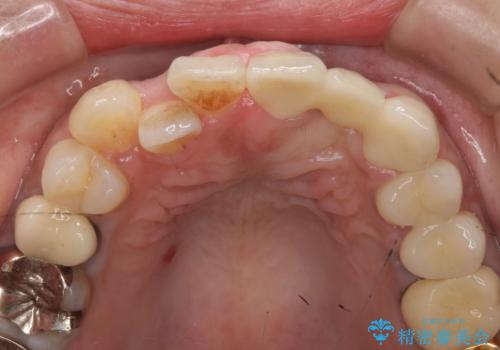

- 左上2番目の歯がグラグラするので診て欲しいといらっしゃった方の症例です。

左上2番目の歯は歯根が破折してため抜歯し、左上123のブリッジによる欠損補綴を行いました。

左上4、5番目の歯は根尖病変を認めたため再根管治療を行い、オールセラミッククラウンによる補綴を行いました。

なお左上4に関しては縁下歯質を改善するため、歯冠挺出を行っております。